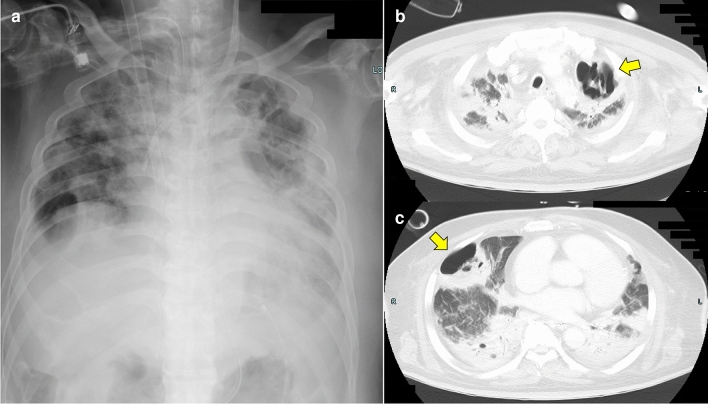

A 60-year-old Japanese man suffered from cold symptoms while traveling in Southeast Asia. The patient visited a hospital in Thailand and was diagnosed with influenza infection. Subsequently, the patient's respiratory condition worsened and he was admitted and treated in the intensive care unit (ICU) of the hospital in Thailand. Since the patient strongly requested to receive treatment in Japan, he returned to Japan while receiving oxygen administration with adequate informed consent. The patient was immediately admitted to our hospital after arriving in Japan, and veno-venous extracorporeal membrane oxygenation was performed to maintain respiratory function. Tazobactam/piperacillin, linezolid, ganciclovir and voriconazole were administered to treat bacterial, fungal, and viral infections. Chest Xp showed bilateral pleural effusions and severe consolidation in the bilateral whole lung fields (Fig. 1a). Chest computed tomography (CT) also showed severe consolidation, pleural effusion, and cavity formation in the bilateral lungs (Fig. 1b, c). The patient was administered dobutamine, noradrenaline, and vasopressin due to cardiopulmonary failure associated with severe inflammation, but his circulatory condition could not be maintained and he died on day 5 of admission. A pathological autopsy was performed to elucidate the causes of severe respiratory failure.

Fig. 1.

Chest Xp and CT. a Bilateral pleural effusions and severe consolidation in the bilateral whole lung fields. b Consolidation in the bilateral upper lobe and a cavitary lesion (arrow) in the left upper lobe. c Consolidation in the bilateral middle lobe and a cavitary lesion (arrow) in the right middle lobe